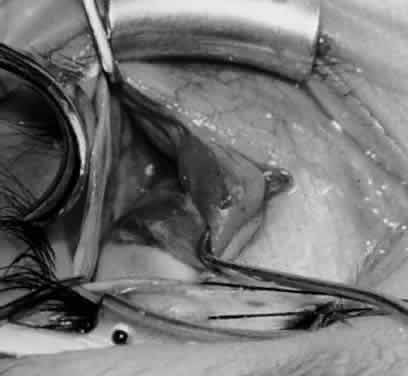

Fig. 12. An Aebli scissor is placed beneath the inferior oblique muscle insertion before it is sectioned from the globe.

Fig. 13. The inferior oblique muscle is sectioned from the globe. A preplaced 6-0 Vicryl suture is attached to the insertion.

Fig. 14. The inferior temporal vortex vein, 8 mm posterior to the temporal insertion of the inferior rectus muscle, is held on a Green muscle hook.

Fig. 15. The placement of sutures within the sclera for a recession procedure of 10 mm. The anterior suture is placed 3 mm temporal and 2 mm posterior to the lateral insertion of the inferior rectus muscle, and the posterior suture is placed 3 mm further posteriorly.

Fig. 16. Two sutures straddle the inferior temporal vortex vein insertion for a 14-mm recession procedure.

Fig. 17. Knots are tied to show the placement. The inferior oblique muscle is held on a Stevens muscle hook.

Fig. 18. The final position, with the inferior oblique muscle recessed 10 mm. The inferior rectus muscle is retracted with a Green muscle hook. As described in the text, the 14-mm recession would place the inferior oblique muscle over the inferior temporal vortex vein, and the 6-mm recession would place the inferior oblique muscle anterior and nasal to this position.

Fig. 19. A 14-mm inferior oblique muscle recession is placed over the inferior temporal vortex vein.

Fig. 20. Optional closure of the incision with a 6-0 Vicryl suture. The incision may be allowed to heal without a suture.